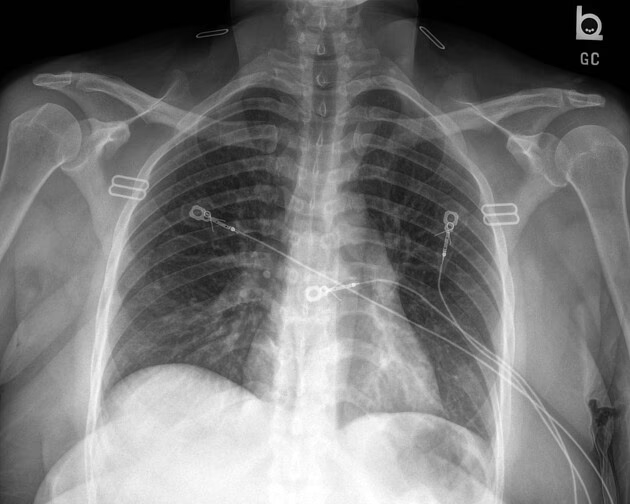

Et røntgenbillede af brystet, også kendt som et thoraxrøntgen, er en hurtig, smertefri og non-invasiv billeddiagnostisk test. Den bruger en meget lille mængde ioniserende stråling til at skabe billeder af strukturerne inde i din brystkasse. Dette inkluderer dine lunger, hjerte, store blodkar, ribben og mellemgulv. Fordi forskellige væv i kroppen absorberer stråling i forskellig grad, kan en radiolog skelne mellem knogler, blødt væv og luftfyldte rum som lungerne. Det er et yderst værdifuldt værktøj til at få et overordnet billede af sundheden i din brystregion.

- Forberedelse: Du behøver ikke at faste eller ændre din daglige rutine. Du kan spise og drikke normalt før undersøgelsen. Du vil blive bedt om at fjerne smykker og andre metalgenstande fra din overkrop, da de kan forstyrre billedkvaliteten.

- Positionering: En radiograf vil guide dig til at stå oprejst foran en flad plade, som kan føles lidt kold. Du vil blive bedt om at presse brystet mod pladen.

- Selve optagelsen: Du skal tage en dyb indånding og holde vejret i et par sekunder, mens røntgenmaskinen sender en stråle gennem din brystkasse. Det er afgørende at stå helt stille for at undgå slørede billeder. Typisk tages der to billeder: et forfra (frontal visning) og et fra siden (lateral visning) for at give et tredimensionelt perspektiv.

Hjerteproblemer

Selvom et røntgenbillede ikke kan diagnosticere et hjerteanfald, kan det afsløre tegn på underliggende hjerteproblemer, der kan forårsage hoste. Dette inkluderer et forstørret hjerte (kardiomegali) eller væske i lungerne (lungeødem), som begge er tegn på hjertesvigt.